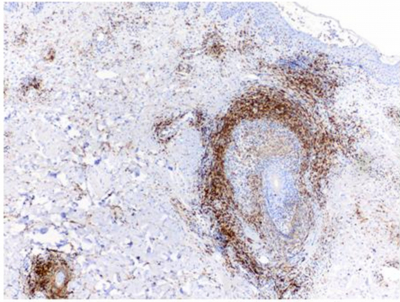

Two sets of biopsies were examined. The initial biopsy (dated 2002) showed a mild perifollicular infiltrate composed of lymphocytes and some eosinophils. A few eosinophils were reported to be present in the epidermis. A diagnosis of eosinophilic folliculitis was made in an outside institution. Subsequent in house biopsies, taken 6 years later, showed a dense lymphocytic infiltrate with prominent folliculotropism. Some epidermotropic cells were also seen. (Figure 2A) The infiltrating lymphocytes displayed mild cytologic atypia (Figure 2B). Plasma cells and eosinophils were also present. Immunohistochemical studies revealed the lymphocytes to be CD3-positive T cells (Figure 2C); rare CD20-positive B cells were identified. The folliculotropic and epidermotropic lymphocytes were mainly CD4 positive (Figure 2D). Scattered CD8-positive cells were seen within the follicles and epidermis (Figure 2E). Diffuse (greater than 75%) positivity for CD25 by the atypical lymphocytes was observed in one of the biopsies. Re-examination of the original biopsy showed a population of atypical, epidermotropic CD3-positive lymphocytes, positive for CD4 and negative for CD8. The epidermotropic and folliculotropic lymphocytes show a CD4:CD8 ratio of about 4:1. A diagnosis of mycosis fungoides, folliculotropic, was made on both sets of specimens. Molecular studies for TCR gamma gene rearrangement identified a monoclonal population, supporting the diagnosis of mycosis fungoides.